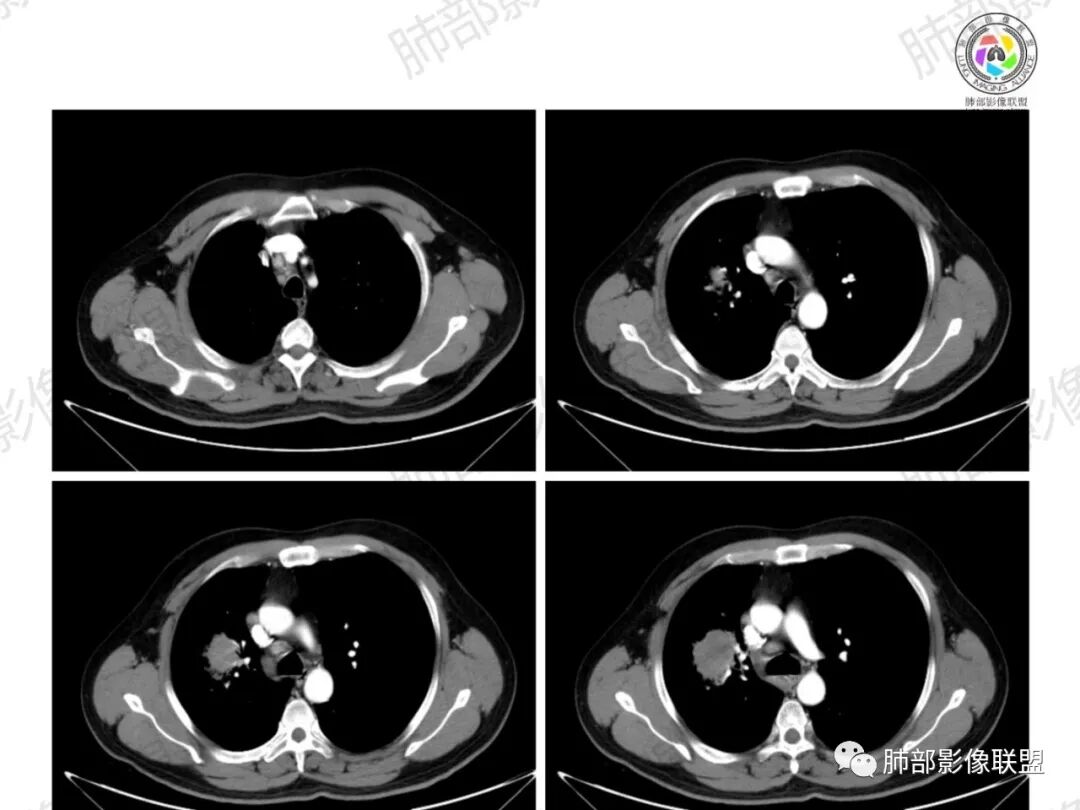

Coke with ice:病变整体收缩平直,毛刺较软,支气管壁增厚。支气管鼠尾状狭窄,于病灶以远可见显示。支气管粘液栓。相邻支气管血管推移明显,磨玻璃边缘模糊,多灶坏死边缘清晰,一部分血管自然穿行,猜个炎性病变。

这个比较大的坏死灶,边缘清晰,看似符合鳞癌坏死。仔细看看这个坏死边界,是血管阻挡引起的边界清晰。其他的病灶内低密度是柱形粘液栓。实性部分强化有轻度延迟强化。病变背景是双上肺的小叶中心结节。病变区的支气管壁是厚的。

妞妞:右肺门区病灶,边缘有GGO,模糊,远端树芽,支气管受阻,有圆钝感,病灶坏死,边缘清楚,实性成分有强化,不像鳞癌强化,首先考虑结核,鳞癌待排,建议支气管镜

良孑:右肺门肿块,有平直,u型凹陷及尖角征,远端可见散发树芽征,有支气管截断,肿块内坏死边界清,似可见围绕坏死的环状强化,综合分析首选炎性病变,TB可能,冇吸烟史,良恶性征象都有鳞癌要鉴别,

多发树芽,病灶边缘模糊的GGO

环形强化

坏死区几乎是寸草不生

纵隔淋巴结肿大并不明显,就这一个肿大较明显,但仍呈椭圆形,中心少许坏死。